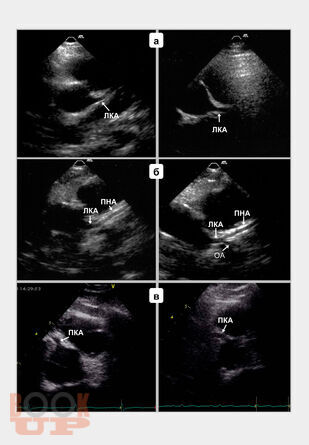

В монографии подробно изложены основные принципы трансторакального ультразвукового исследования магистральных коронарных артерий, включая методические и технические особенности визуализации, обсуждены параметры ламинарного, турбулентного и коллатерального коронарного кровотока, способы оценки и алгоритмы диагностики коронарных стенозов и окклюзий. Также представлены методика определения, способы расчета и критерии оценки резерва коронарного кровотока при трансторакальной допплерографии, показаны диагностическая и прогностическая роли показателя при выявлении гемодинамически значимых коронарных стенозов, окклюзий и определении лечебного эффекта интракоронарных интервенционных вмешательств. Книга рассчитана на кардиологов, врачей функциональной и ультразвуковой диагностики, эндоваскулярных хирургов, патофизиологов, студентов медицинских вузов.